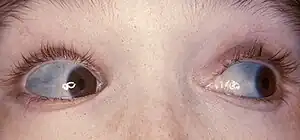

| The classic blue sclerae of a person with osteogenesis imperfecta | |

| Symptoms | Bones that break easily, blue tinge to the whites of the eye, short height, loose joints, hearing loss[1][4] |

- Poor muscle tone

- Discoloration of the sclera (whites of the eyes), usually giving them a blue-gray color. The blue-gray color of the sclera is due to the underlying choroidal veins which show through. This is due to the sclera being thinner than normal because the defective Type I collagen is not forming correctly.

- Discolouration of the sclera (the 'whites' of the eyes are blue)